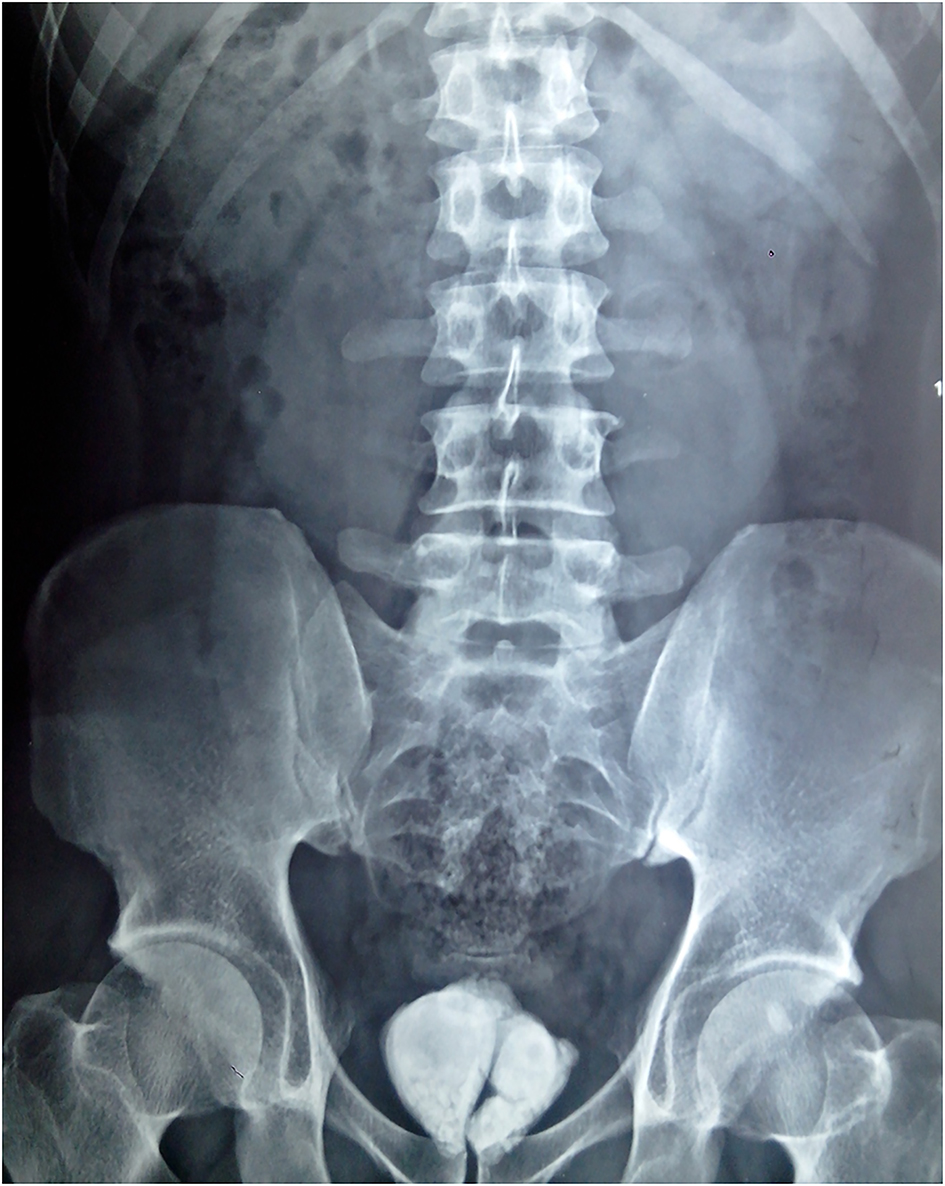

Ureteric Calculus | Image | Radiopaedia.org

Ureteric calculus | Image | Radiopaedia.org radiopaedia.org

ureteric calculus radiopaedia stone version